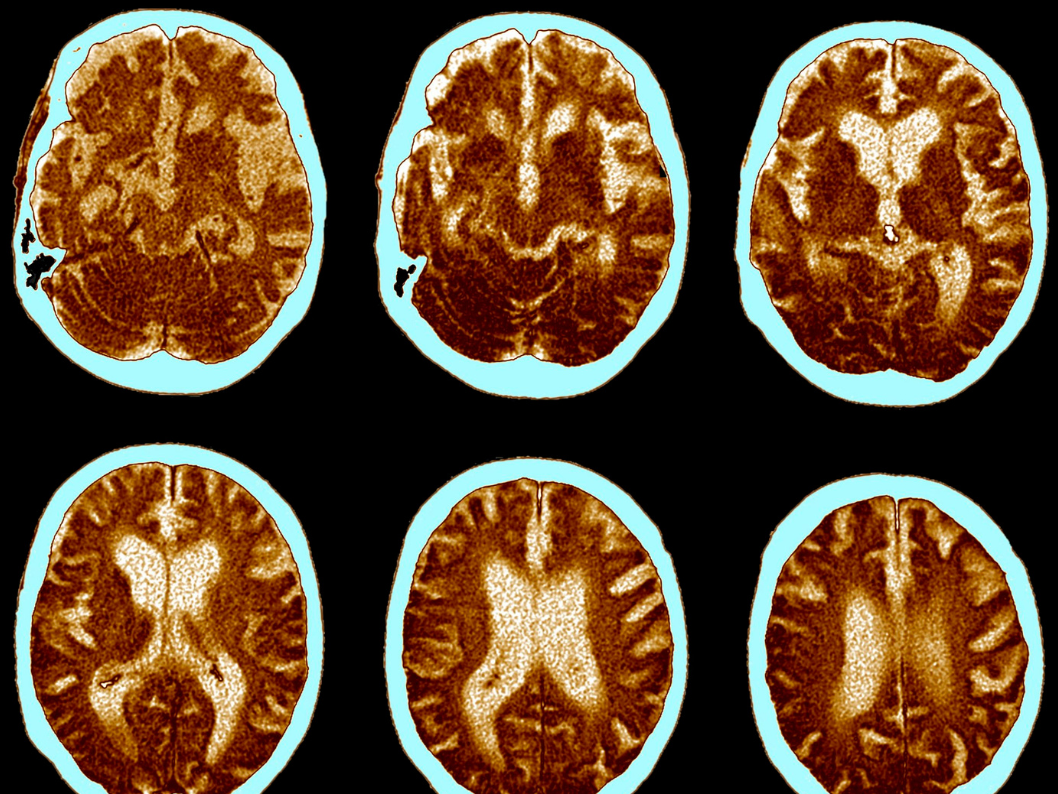

Ahí, el cortisol libre, influye directamente en el funcionamiento del cerebro y genera cambios en la respuesta inmunológica. A su vez, puede desregular el HPA, aumentando el riesgo de depresión y exacerbando la neuropatología de esta enfermedad neurodegenerativa. Por otro lado, también afecta al hipocampo, causando atrofia y alterando el nacimiento de nuevas neuronas.

Así que sí, el estrés crónico puede acelerar el proceso de envejecimiento y afectar los sustratos neurales, además de contribuir al deterioro cognitivo y la demencia. De este modo, podría constituirse como un factor de riesgo en enfermedades neurodegenerativas como lo es la enfermedad de Alzheimer.

La búsqueda de conexiones entre el estrés y el desarrollo de la enfermedad de Alzheimer es crucial para comprender mejor los mecanismos subyacentes de la enfermedad. Los niveles de cortisol salival, que reflejan los niveles de cortisol biológicamente activo en el cuerpo, se han identificado como un marcador prometedor para el deterioro cognitivo asociado con la enfermedad. Y, con ello, se ha documentado que el estrés puede afectar los sistemas de memoria y la capacidad de recordar eventos pasados, lo que sugiere la relación entre el estrés y la función cognitiva.

En cuanto a los efectos del estrés, se ha observado que el estrés agudo puede tener ciertos beneficios adaptativos y mejorar el funcionamiento de la memoria en situaciones específicas. Por ejemplo, en situaciones de peligro inmediato, el estrés agudo puede potenciar la memoria para recordar detalles importantes. Sin embargo, el estrés crónico, que implica una exposición prolongada a situaciones estresantes, se ha asociado con una disminución en la capacidad de codificar y consolidar la memoria. Esto sugiere que el estrés prolongado puede tener efectos negativos en la función cognitiva a largo plazo, lo que podría ser relevante en el contexto de la enfermedad de Alzheimer y otros trastornos neurodegenerativos.